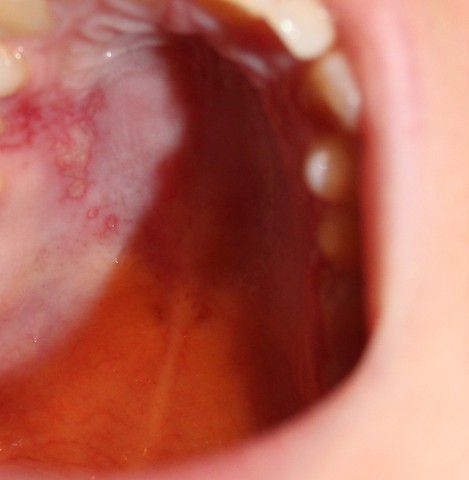

на нёбе какое-то красное раздражение, болит как расцарапанный ожег. была температура, болит правая гланда и появилась простуда на губе. это все как-то связано?? что это и как это лечить?